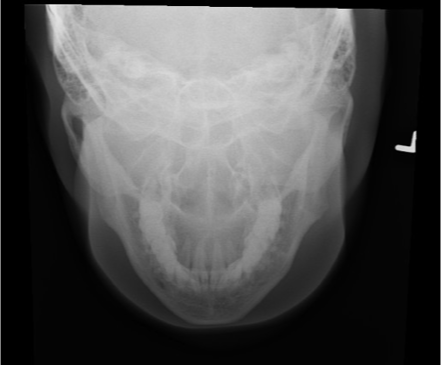

PA projection of skull

PA of skull